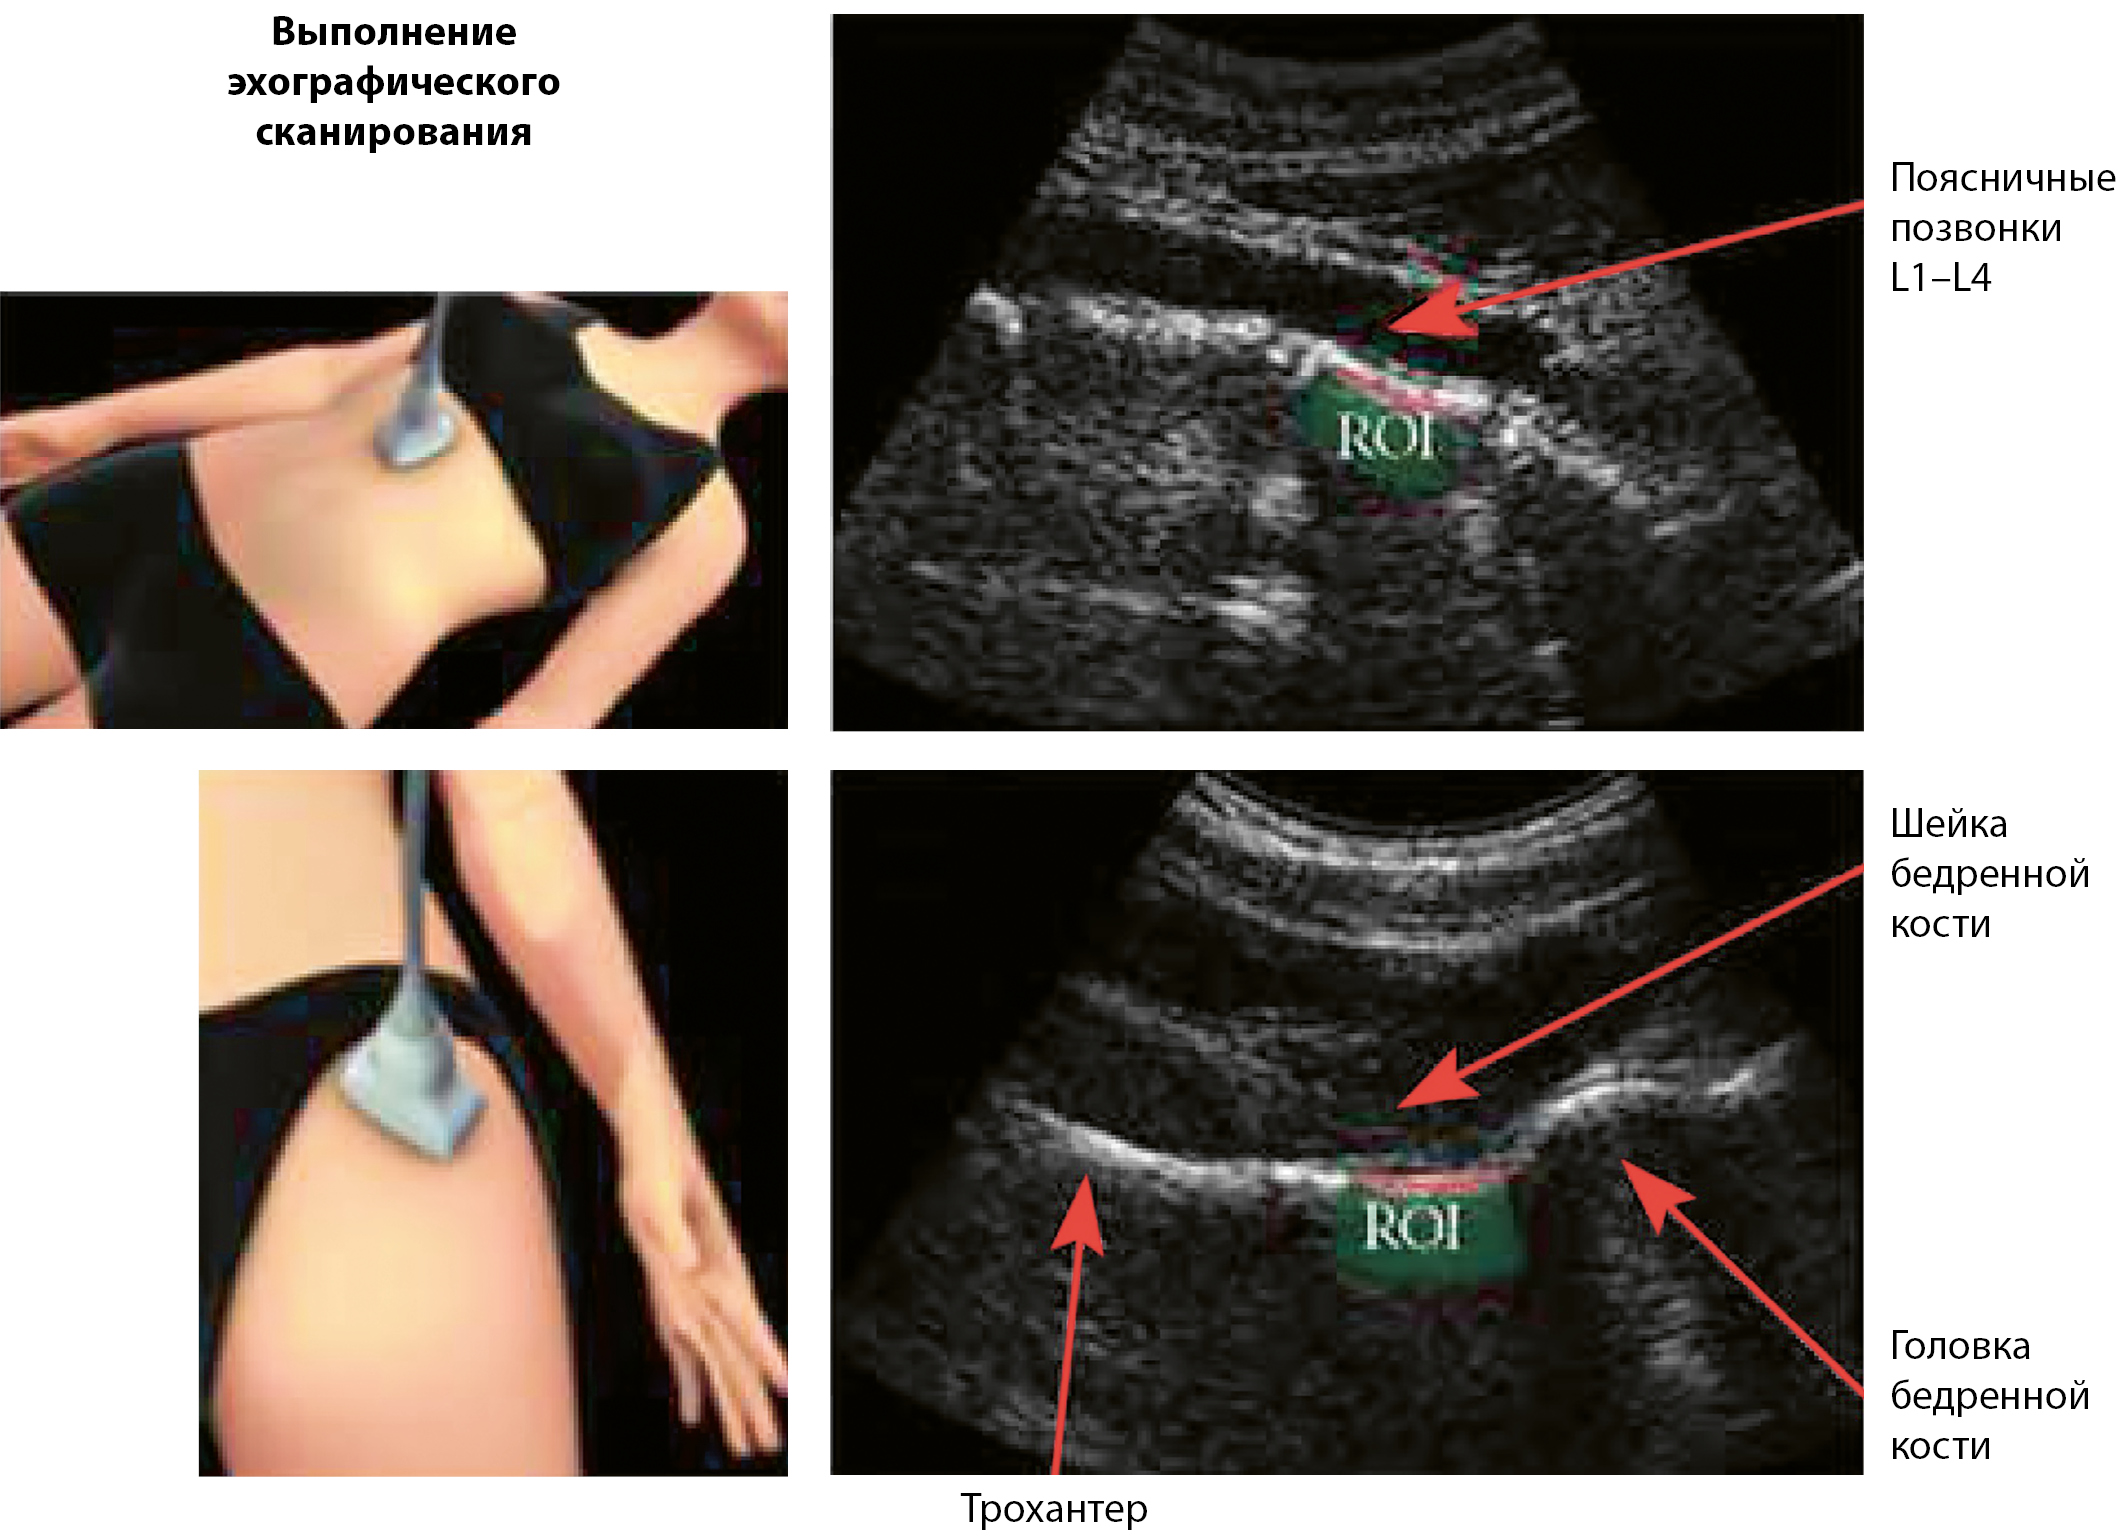

При проведении исследования сканированию подвергаются аксиальные участки скелета, как и при рентегновской денситометрии — проксимальный отдел бедренной кости и поясничные позвонки. Визуализация осуществляется путем сканирования искомых областей датчиком 3,5 МГц через переднюю брюшную стенку и/или область верхней трети бедра с подбором параметров фокуса и глубины в зависимости от конституции пациента (рис. 1) [17].

Рисунок 1. Радиочастотная эхографическая мультиспектрометрия. Технология сканирования.